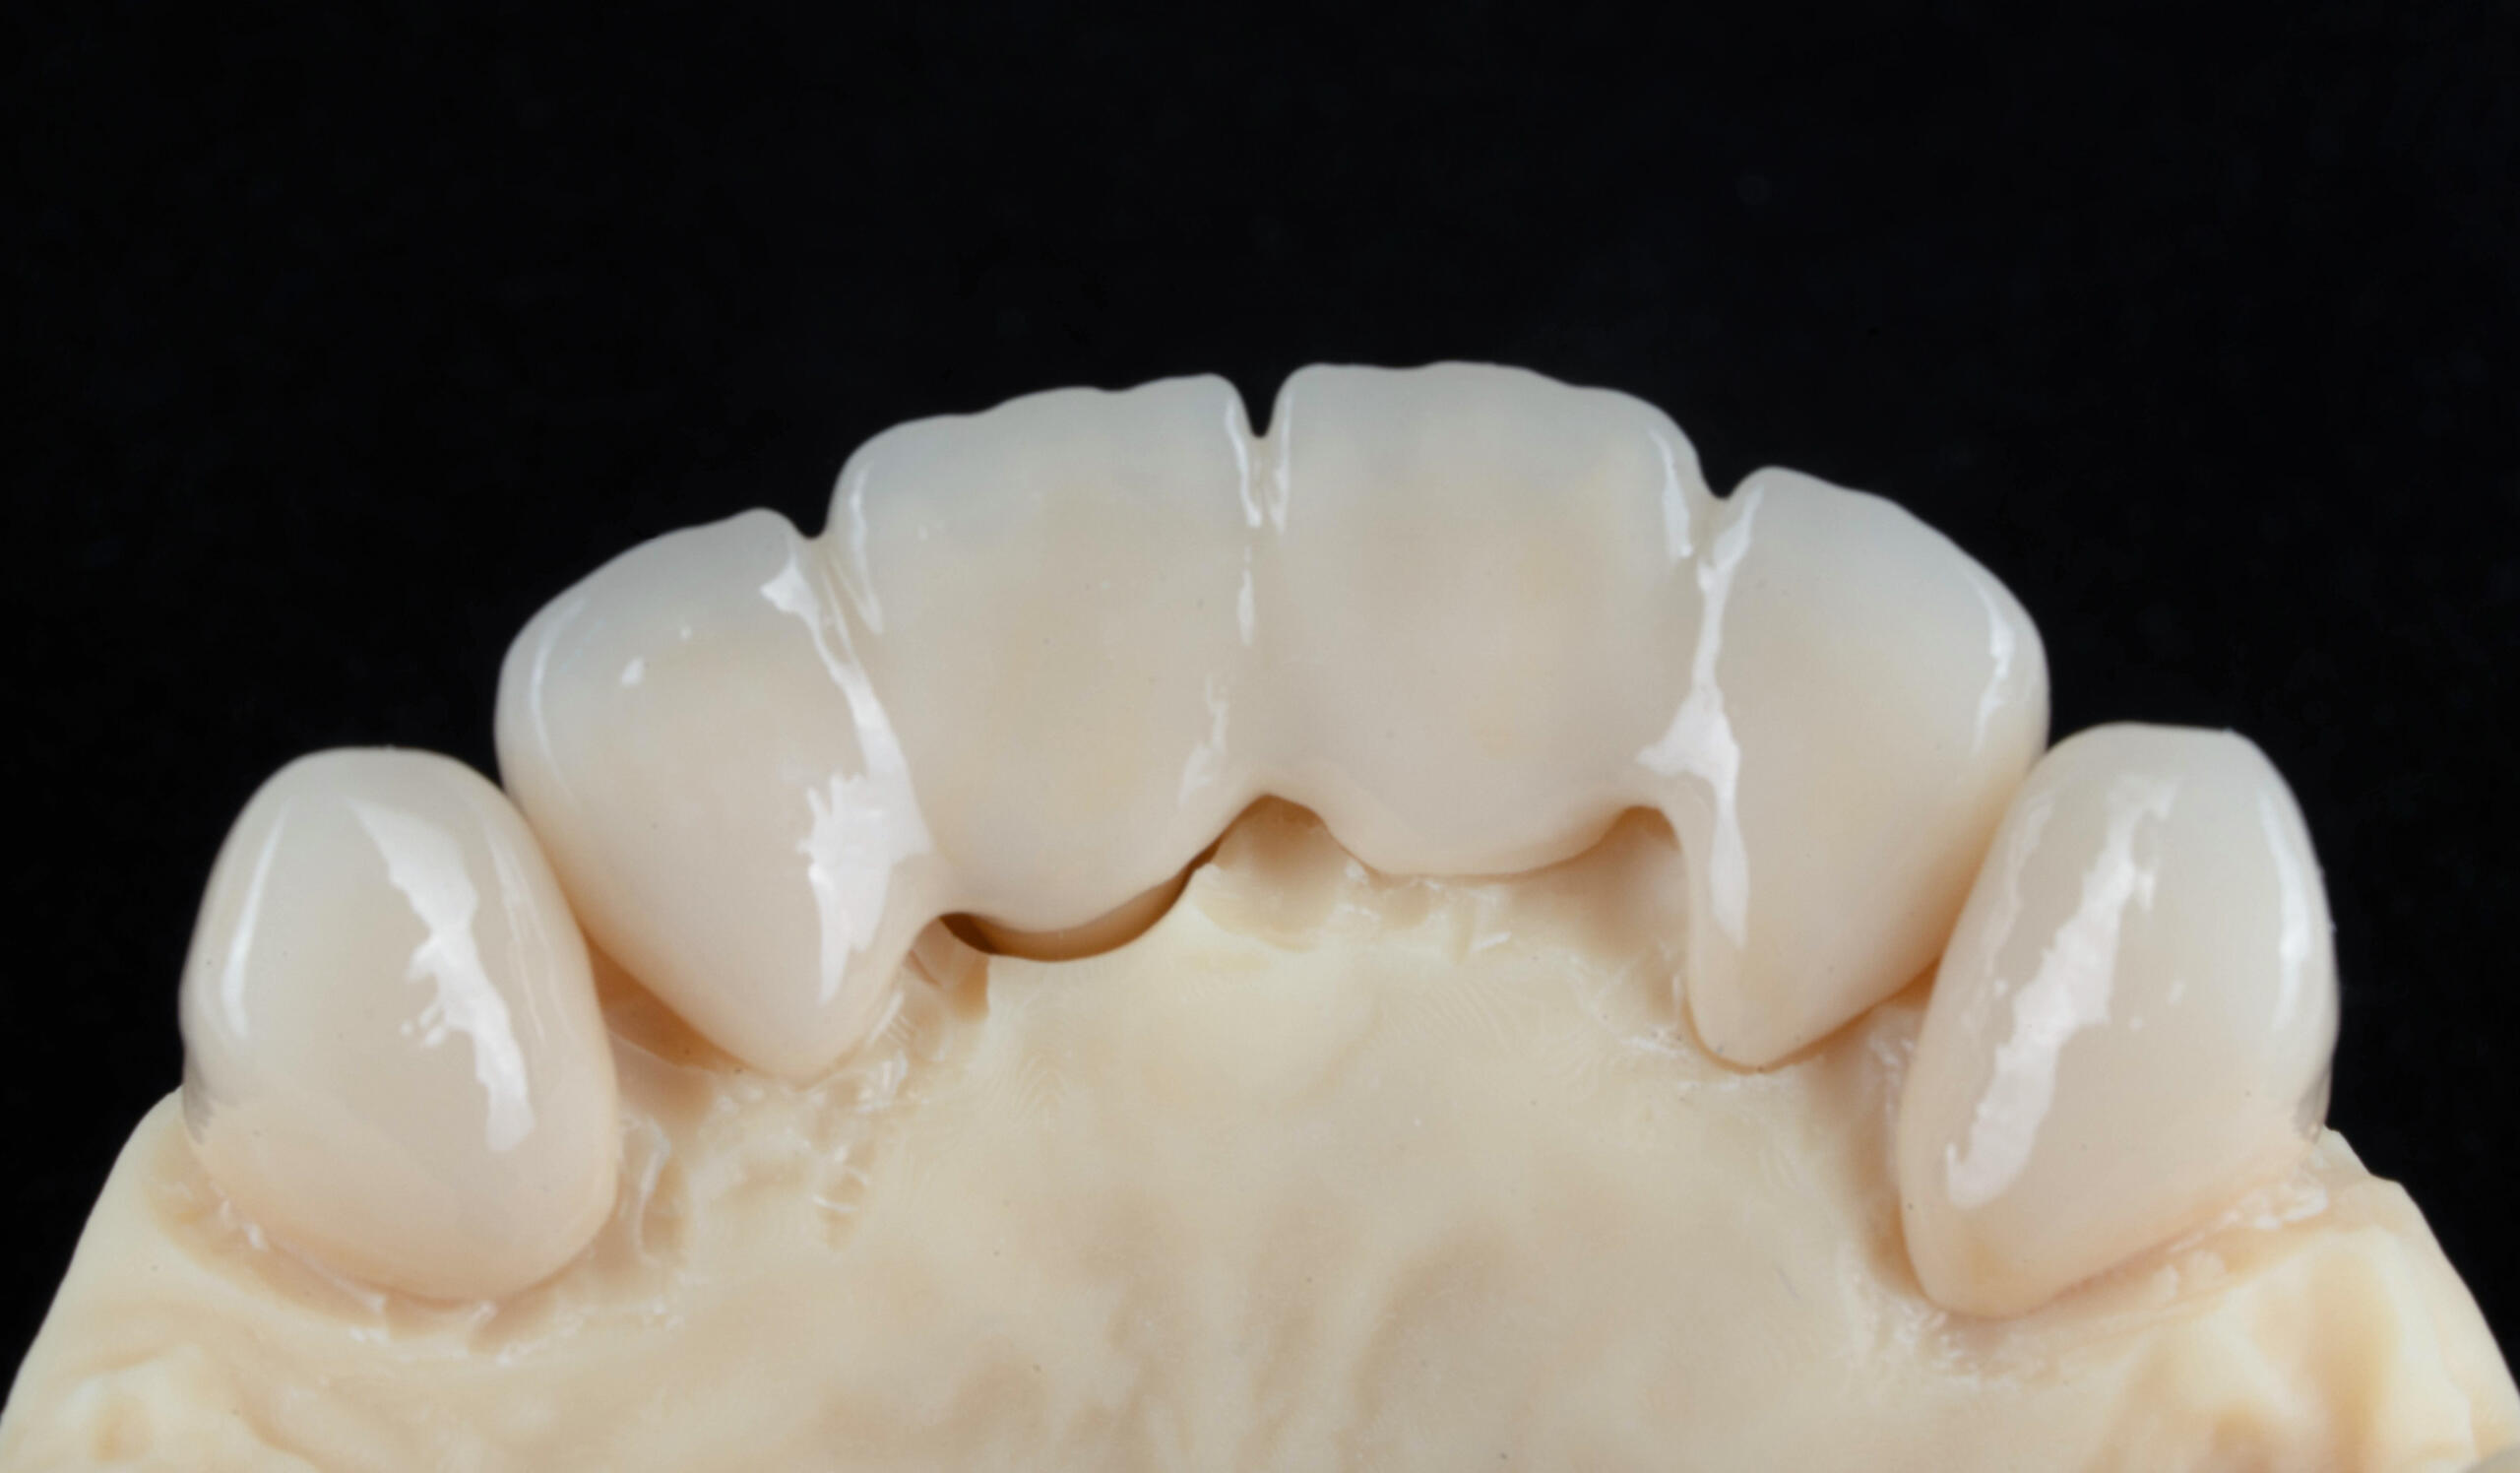

- Zirconiu – estetică premium, rezistență ridicată, biocompatibilitate 100%

- Ceramică presată – transluciditate naturală, ideală pentru zona frontală

- Proba lucrării și adaptarea funcțională și estetică